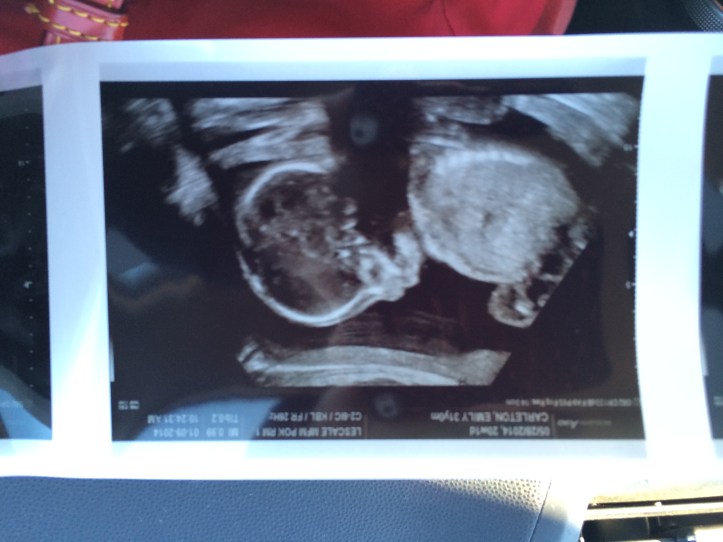

In the 43rd episode of the Pop Poppa Nap Cast you find out the sex of our new baby, hear me talk about how different the second pregnancy is over the first and the eternal problem of finding a good boy name.

Here’s the little guy in the flesh!